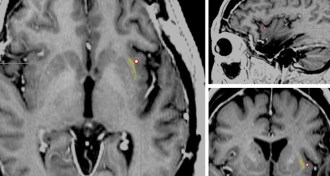

Tadpole eye transplant shows new way to grow nerves

Wiring replacement organs into the body may be as easy as discharging a biological battery, new experiments with tadpoles suggest.